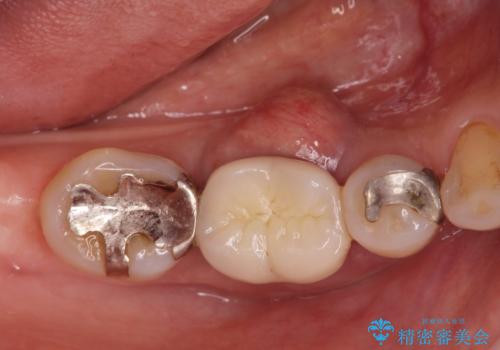

- 歯茎が腫れて痛いとの事で来院。

保存できない状態でしたので抜歯をして歯槽堤保存術を行いました。その後大臼歯部にインプラント治療を行いました。